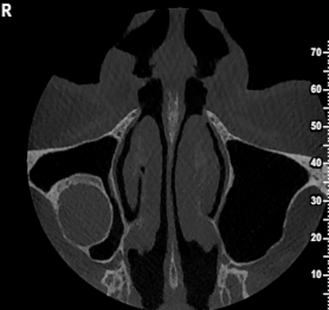

Περίπτωση ιδιαίτερα εκτεταμένης υπολειμματικής κύστης που καταλαμβάνει σχεδόν όλο το δεξιό ημιμόριο της άνω γνάθου εμπλέκοντας και το δεξιό ιγμόρειο άντρο σε γυναίκα ασθενή ηλικίας 75 ετών.

Η κύστη καταλαμβάνει πλήρως τη φατνιακή ακρολοφία στην οπίσθια δεξιά περιοχή της γνάθου και έχει προκαλέσει ιδιαίτερα εκτεταμένη υπέγερση του εδάφους του ιγμορείου άντρου προβάλλοντας εντός αυτού και καταλαμβάνοντας μεγάλο τμήμα της αεροφόρου του κοιλότητας.

Παρατηρείται επίσης ιδιαίτερα εκτεταμένη έκπτυξη και λέπτυνση του πλαγίου τοιχώματος του ιγμορείου άντρου, καθώς και των συμπαγών πετάλων της φατνιακής ακρολοφίας.